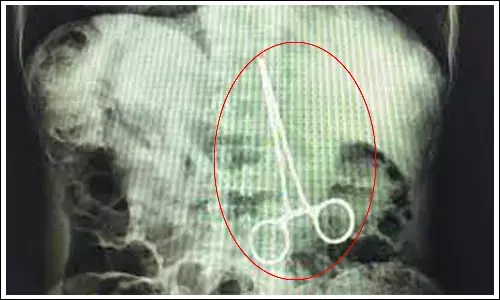

డెలివరీకి వచ్చిన మహిళకు ఆపరేషన్‌.. కడుపులో కత్తెర వదిలేసిన వైద్యులు

by Telugupost Desk17 Aug 2023 9:46 AM IST